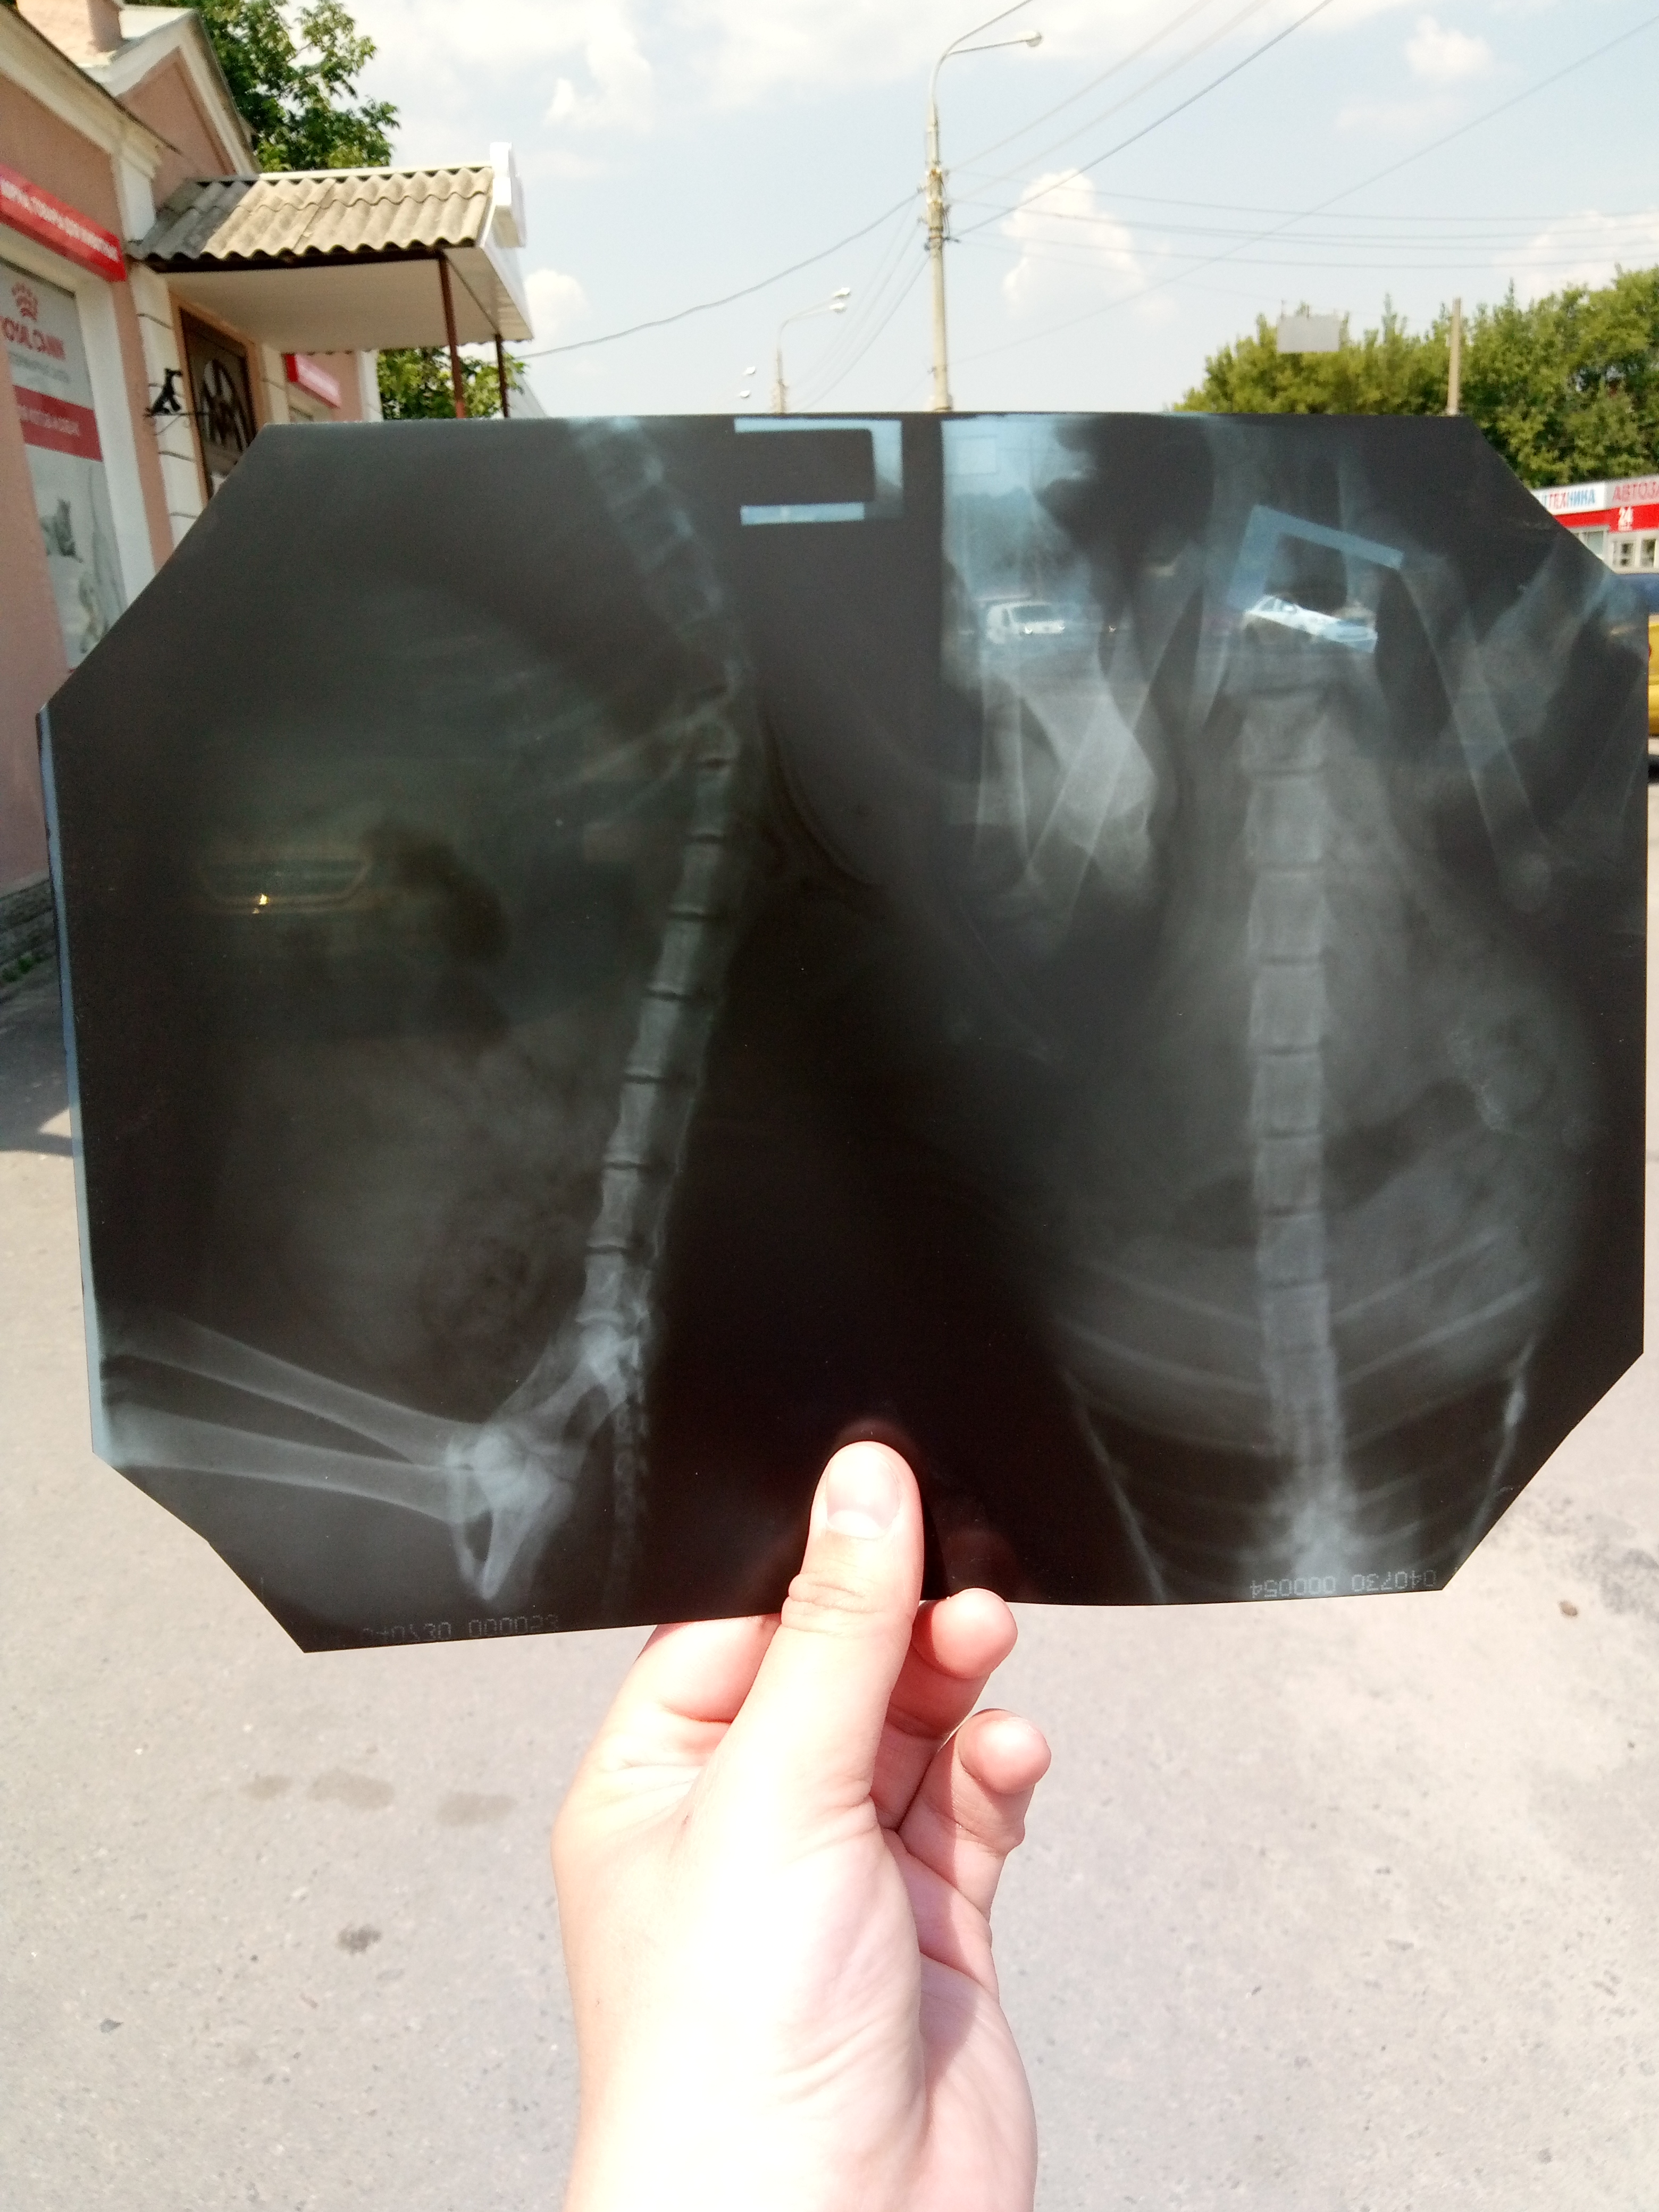

Мавис - Ущемление корешков спинного мозга, частичный паррез пояса задних конечностей, отодекоз

Ли - герпес вирус